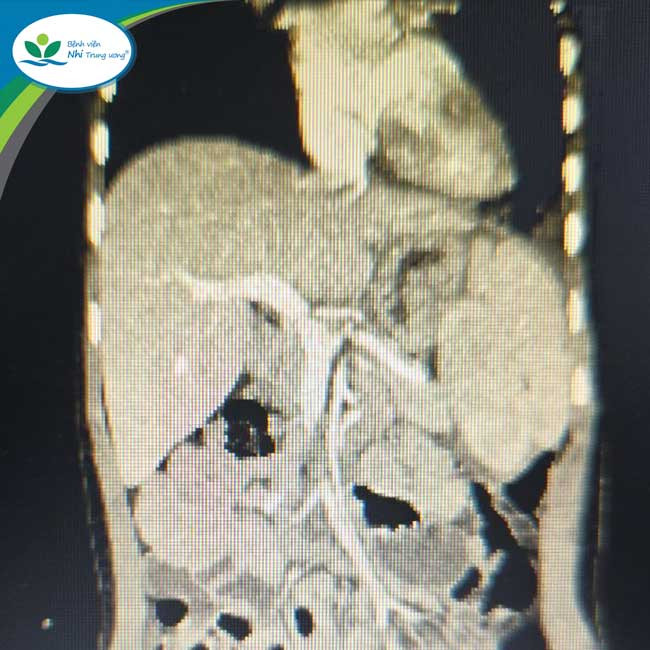

Trước đó, trẻ vào viện vì đau tức ngực và nhiễm khuẩn hô hấp tái diễn nhiều lần. Trẻ được các bác sĩ thăm khám lâm sàng, chụp X-quang và chụp cắt lớp vi tính lồng ngực, hình ảnh quan sát thấy là thoát vị cơ hoành bên trái với tạng thoát vị là lách, đại tràng, ruột non, kèm theo thận trái lạc chỗ trên lồng ngực.

| Thận thoát vị trên lồng ngực - Ảnh BVCC |